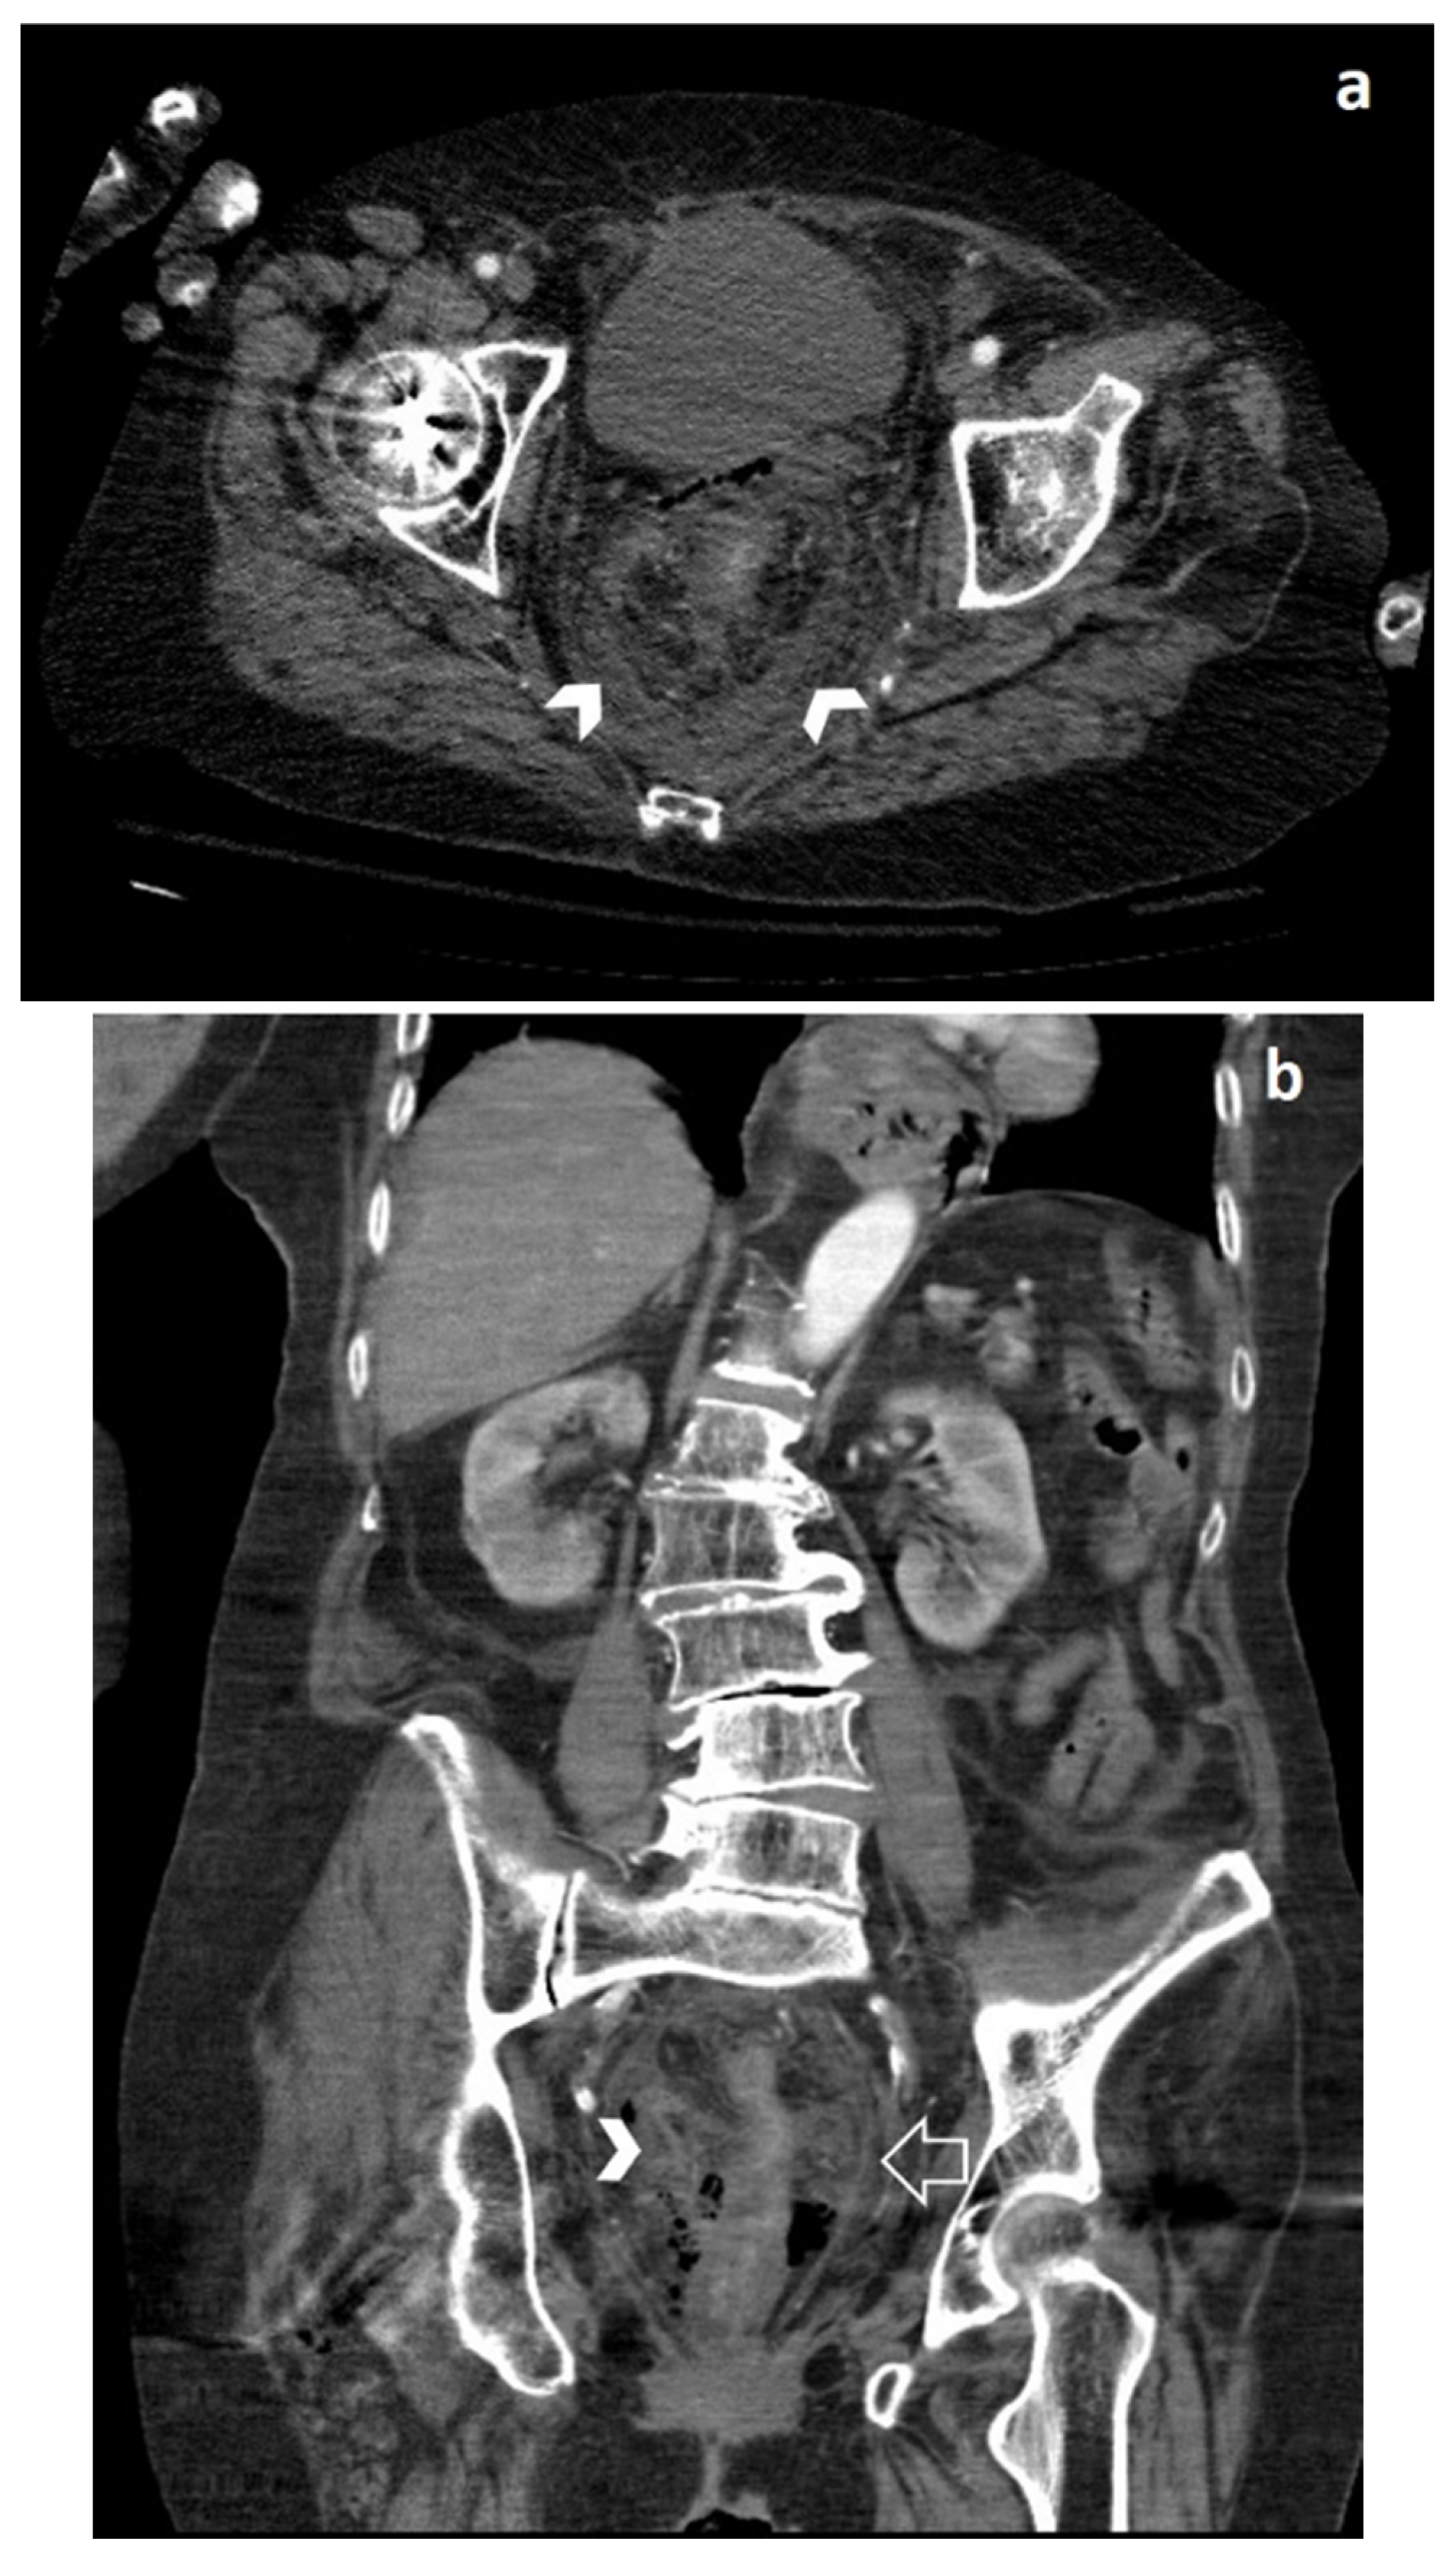

Spontaneous Rectal Perforation in a Patient with SARS–CoV-2 Infection

2. Case Report